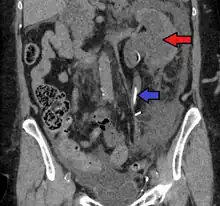

CT scan of bilateral hydronephrosis due to a bladder cancer

Massive hydronephrosis as marked by the arrow.- Renal ultrasonography of hydronephrosis[14]

- Stone causing hydronephrosis[14]

- Urine jets[14]